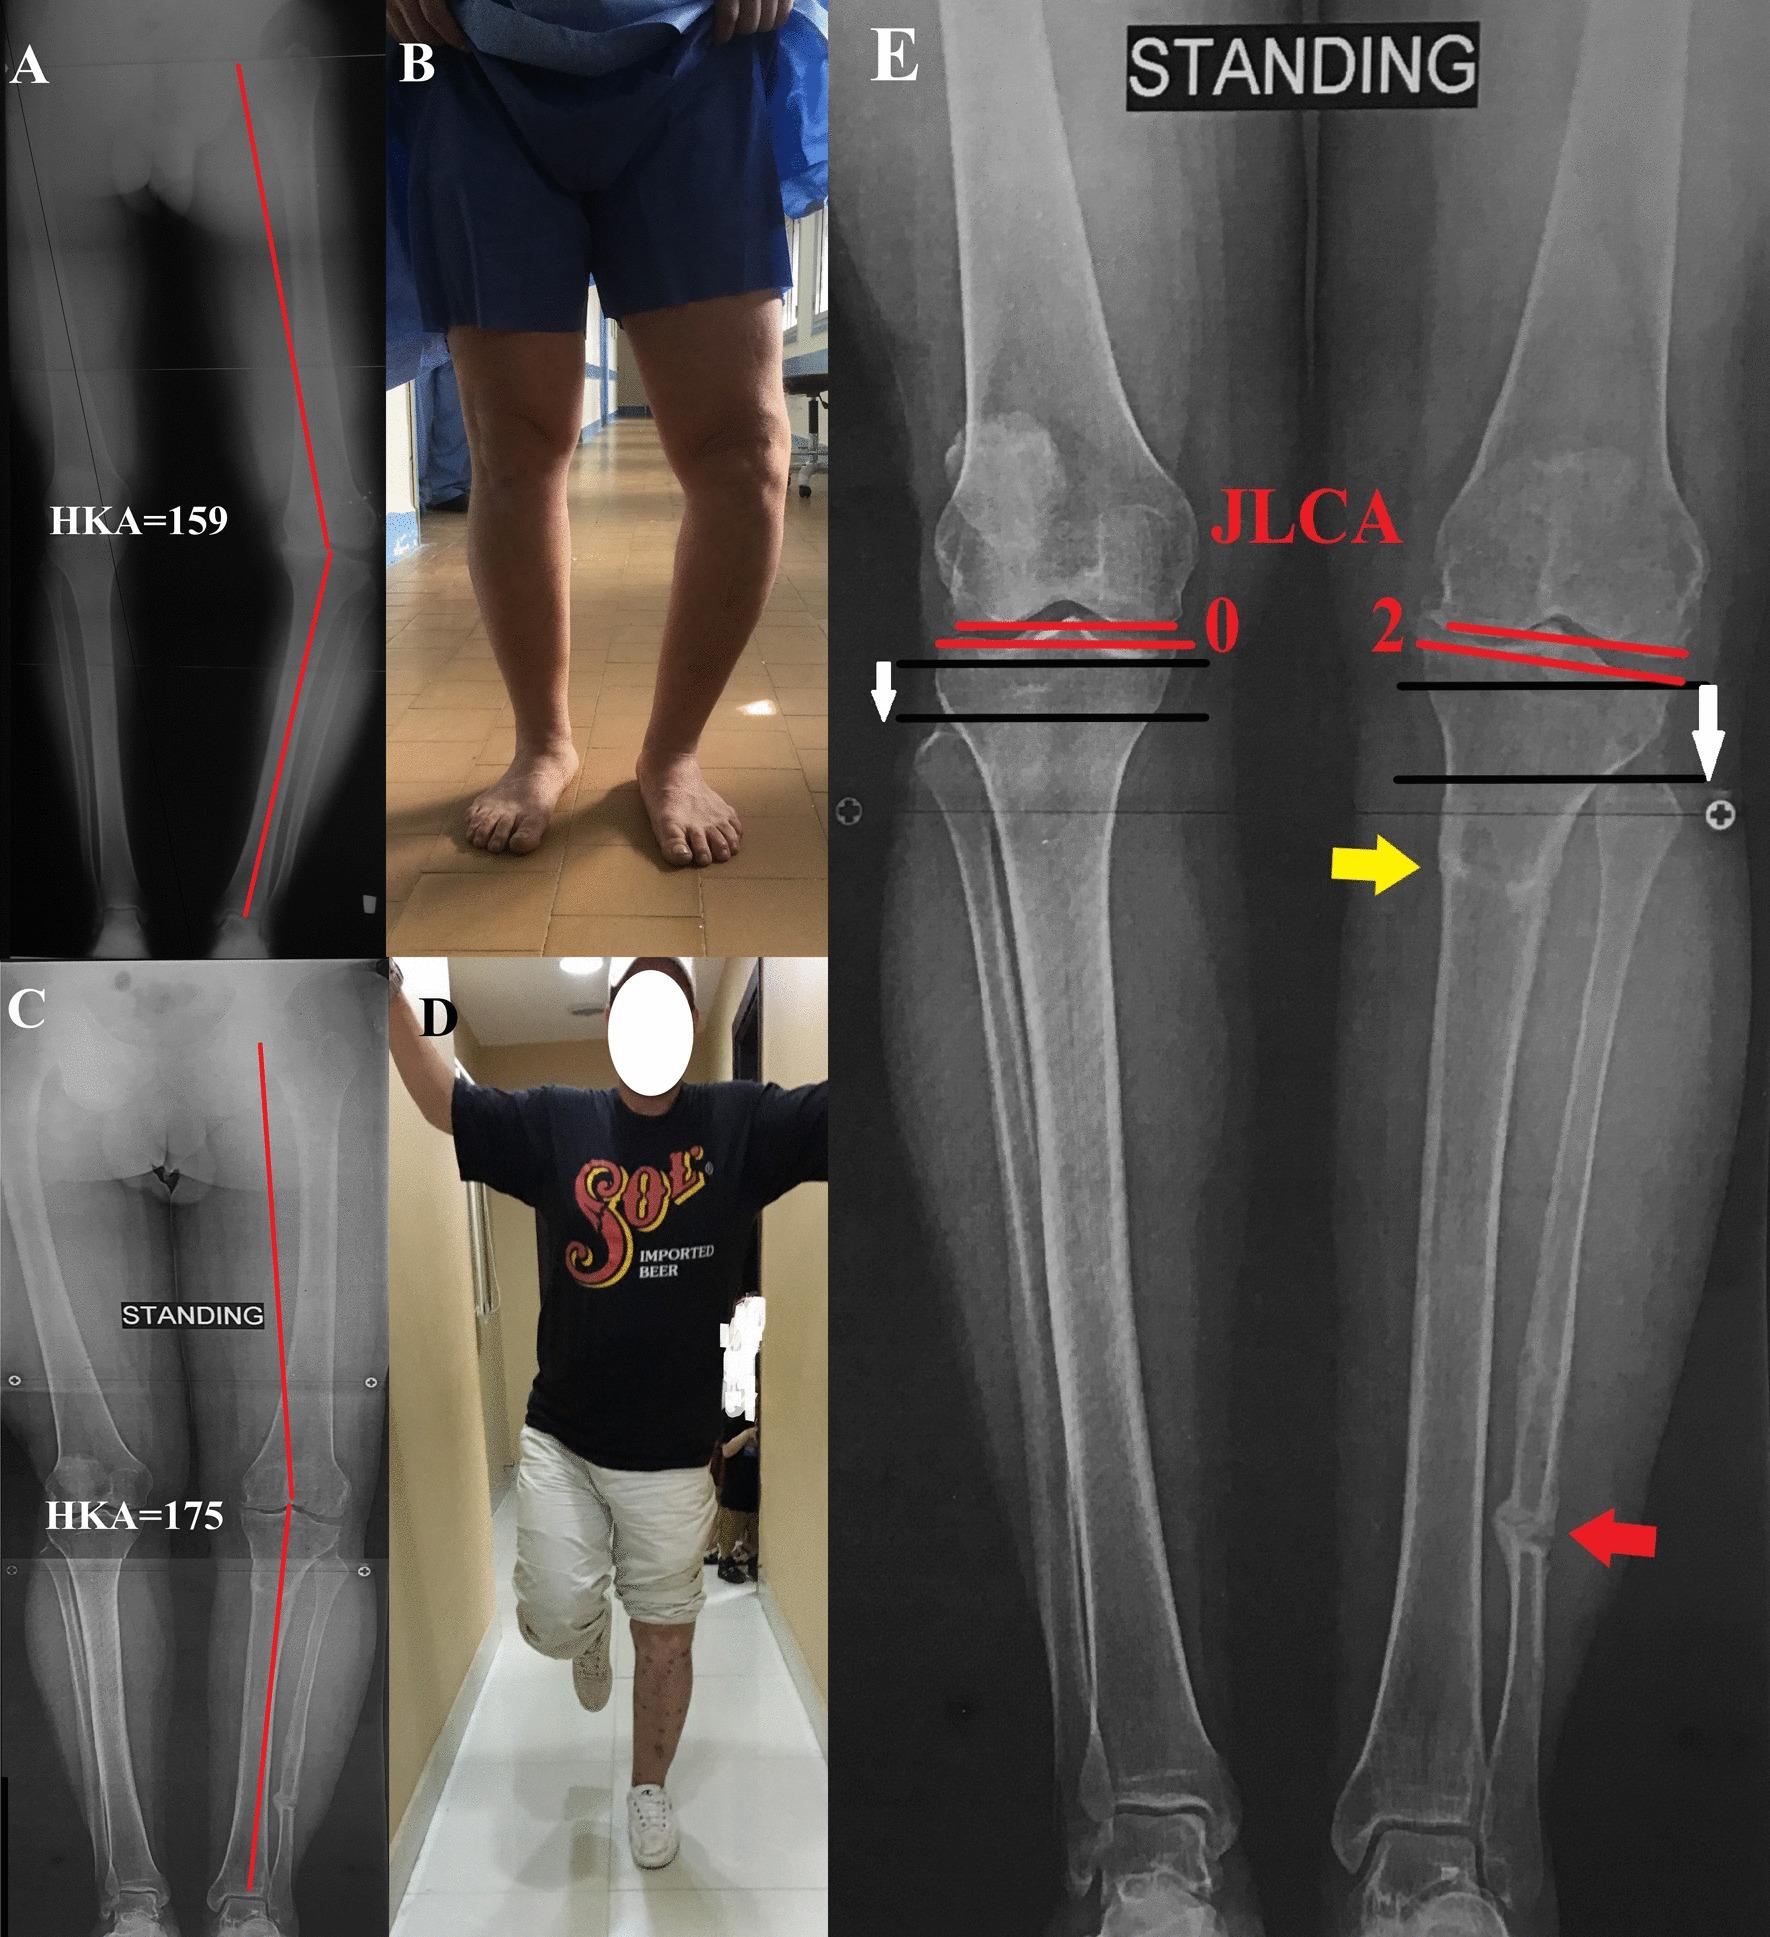

A prospective case series study included 12 adult patients with a mean age of 25.2 ± 8.1 years who presented with GV deformity associated with lateral thrust. They were evaluated clinically using the "hospital for special surgery" (HSS) knee scoring system. Radiological evaluation was performed using long film from hip to knee to ankle (HKA) radiographs; the overall mechanical alignment was measured as the HKA angle, the upper tibial deformity was measured as the medial proximal tibial angle (MPTA), and the joint line convergence angle (JLCA) was measured. Surgical technique included using Ilizarov for MWOHTO below the level of the tibial tubercle, acute correction of the GV deformity, fibular osteotomy, and gradual distalization of the proximal fibula.

After a mean follow-up of 26.3 ± 6.4 months, all osteotomies were united. All patients achieved fibular osteotomy site bony union except two with a fibrous union. The HSS score showed improvement from a mean preoperative score of 88.7 ± 7.6 to a postoperative 97.3 ± 3.9 (P < 0.05). The overall mechanical lower limb alignment improved significantly from a mean preoperative HKA of 164.5 ± 3.2 to a postoperative 178.9 ± 1.6 (P < 0.05). The MPTA improved significantly from 74.6 ± 4.1 to 88.9 ± 2.3, as well as the JLCA from 12.17 ± 1.9 to 2.3 ± 1.7 (P < 0.05). Grade 1 pin tract infection was developed in four patients and was treated conservatively. In two patients, mild pain over the fibular osteotomy site was relieved over time. The lateral thrust reoccurred at the last follow-up evaluation in the two poliomyelitis patients.